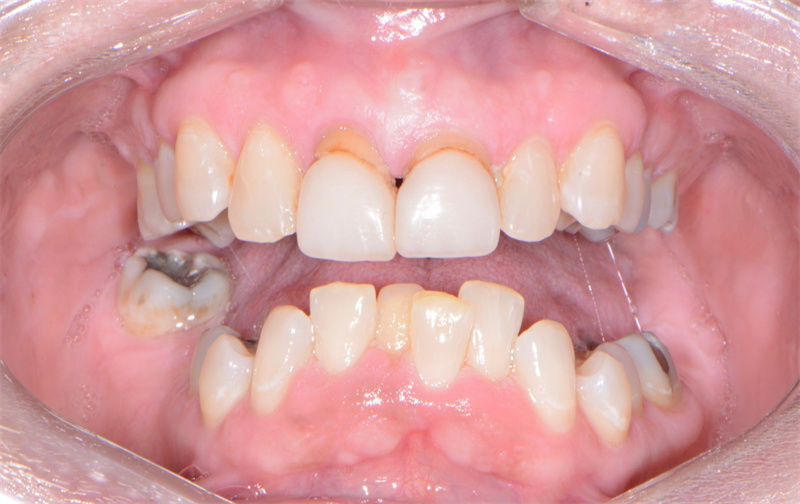

口內(nèi)戴牙照片